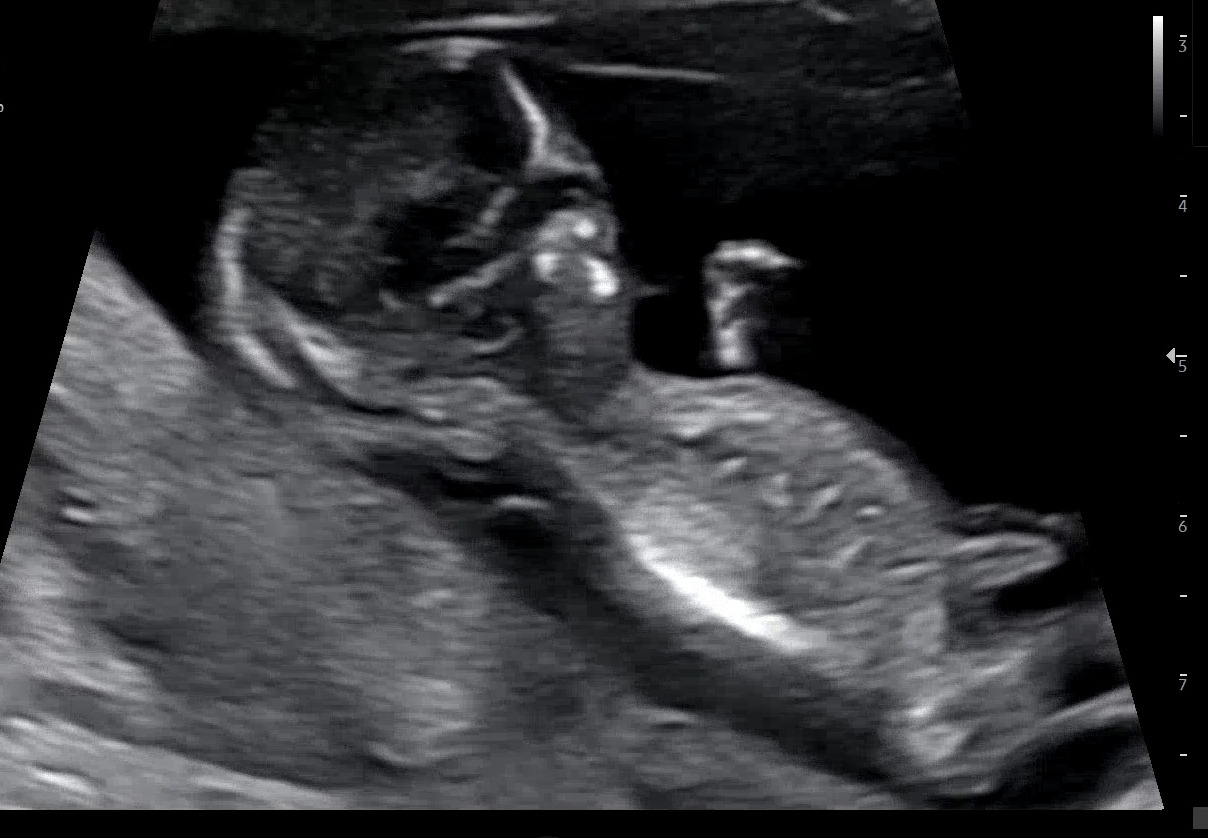

벌써 임신 후기인 31주차이다. 테스트기의 선명한 두줄을 확인하고 얼떨떨한 마음으로 출근을 했던 게 엊그제 같은데, 벌써 만삭처럼 부른 배를 보고 있으면 시간이 얼마나 빠른지- 또 문득 실감하게 된다.

적절한 표현일지 모르겠지만, 이제 제법 큰 몸집으로 쿵쿵거리는 아기의 태동때문에 꿀렁거리는 배를 보고 있으면 꼭 내 배가 시한폭탄인 기분이 든다. 터지기전 빨갛게 빛을내며 요란하게 타들어가는, 게임 아이템으로나 쓰일 것 같은 쇠구슬처럼 동그란 그 폭탄말이다. 그 폭탄은 시간이 지날수록 존재감을 뚜렷하게 드러내며 점점 불러오고, 이제 곧 뻥- 5월이 되면 폭죽처럼 터져 예쁜 아가를 빚어내겠지.